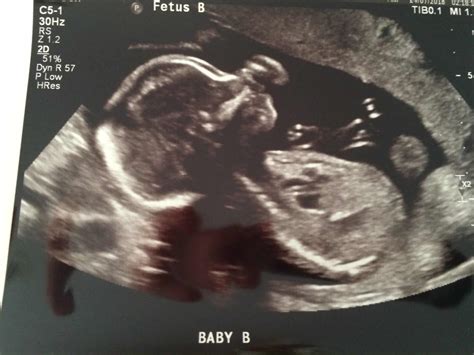

• Multiple Pregnancies: If you are carrying multiples, the scan may take longer, and additional assessments may be required.

• High-Risk Pregnancies: For high-risk pregnancies, additional scans and monitoring may be recommended.

• Genetic Testing: Depending on the results of the 20 week pregnancy sonography, genetic testing may be recommended to rule out any chromosomal abnormalities.